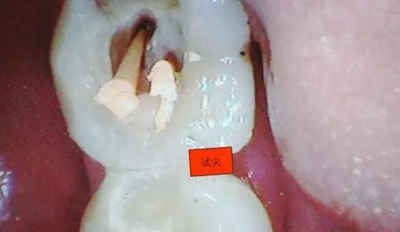

圖三

剛開始懷疑有增生的牙體組織,其實就是髓石。

3.開髓去腐后,髓腔基本就是這樣,在頰側近遠中都有根管口顯示,初步用8號C+銼去試探性探查根管,沒有阻力感,以為就是c型根管,舌側用C+銼時有阻力感覺,接上測量儀去探查根管,以防C+銼探通后超出根尖孔,最后舌根長度16mm*15號K銼(16.5mm*8號C+銼),機擴F2。接下來著重頰側的根管尋找,后來在頰側近遠中插入K銼時總覺得K銼尖段都指向一個位置,感覺不對,再次讀X線片,后來發(fā)現(xiàn)術前沒有仔細查看X線片,以及未回顧這位患者年齡,也就忘記牙齒的增齡性改變的含義。髓腔之所以小或者不清楚,一個因為年齡增加的原因二是因為牙齒長期受到外界物理化學刺激所導致髓腔變小,甚至沒有髓腔顯影。本病例患者,髓腔有大概顯影,但髓室里好像有增生的牙體組織,其實就是髓石。并且和髓室底相連接。如果不注意,有可能按常規(guī)預備方法進行預備。

4.接著與患者溝通后,同意繼續(xù)去除髓石,用細小的安全端金剛砂車針輕微的去除,沿著弧形方向切割,去除后發(fā)現(xiàn)不是2個根管口,而是一個根管口,有點類似下頜6遠中根管口的樣子。(遠中頰根16mm*15號K銼)